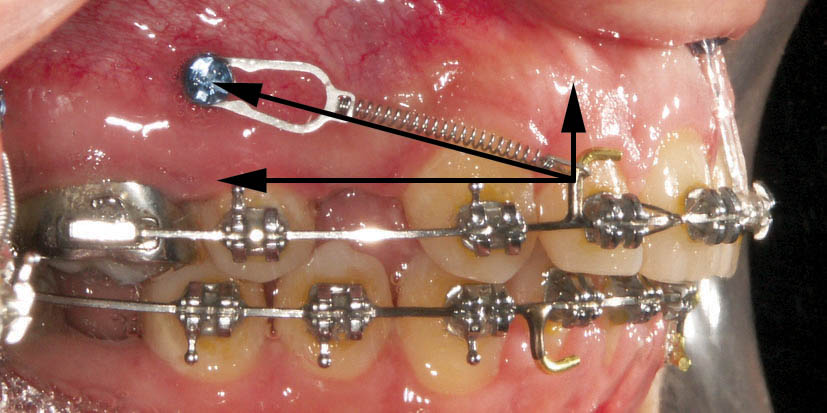

وقتی مینی اسکرو میگذارید در زمان بستن فضا یک فنر از آن به روی هوک آرچوایر میگذارید. این نیرو به دو مولفه دیستاله کننده و اینترود کننده تقسیم میشود (شکل 216-1). نیرو دیستاله کننده باعث بسته شدن فضا و نیروی اینترود کننده باعث اینترود قسمت قدامی میشود که خود مانع بروز دیپ بایت میگردد. این حالت در زمانی که دو طرفه مینی اسکرو دارید خوب است، اما اگر در یک سمت کار گذاشتهاید، در تعداد محدودی از بیماران در حین بسته شدن فضا در آن سمت اپن بایت (به خاطر بردار اینترود کننده) خواهید داشت. پس در زمانی که یک طرفه مینی اسکرو میگذارید از هوکهای بسیار بلندی که اصطلاحاً به آن Squiggly (شکل 217-1) میگویند استفاده کنید تا بخاطر طول بلند آن بردار اینترود کننده به حداقل برسد.

شکل 216-1: تجزیه نیروی فنر از مینی اسکرو به هوک آرچ وایر